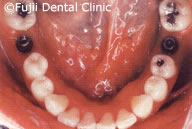

ヘビースモーカーであったために、禁煙してもらい、歯のクリーニングやブラッシング指導後、およそ2年間かけて左上犬歯と左下第一小臼歯以外すべての歯を抜歯し、インプラントの埋入手術を行いました。左右上顎臼歯部はサイナスリフトなどを併用し、インプラントによる咬合の再構築を試みました。

| 術後パノラマ写真および口腔内写真 |